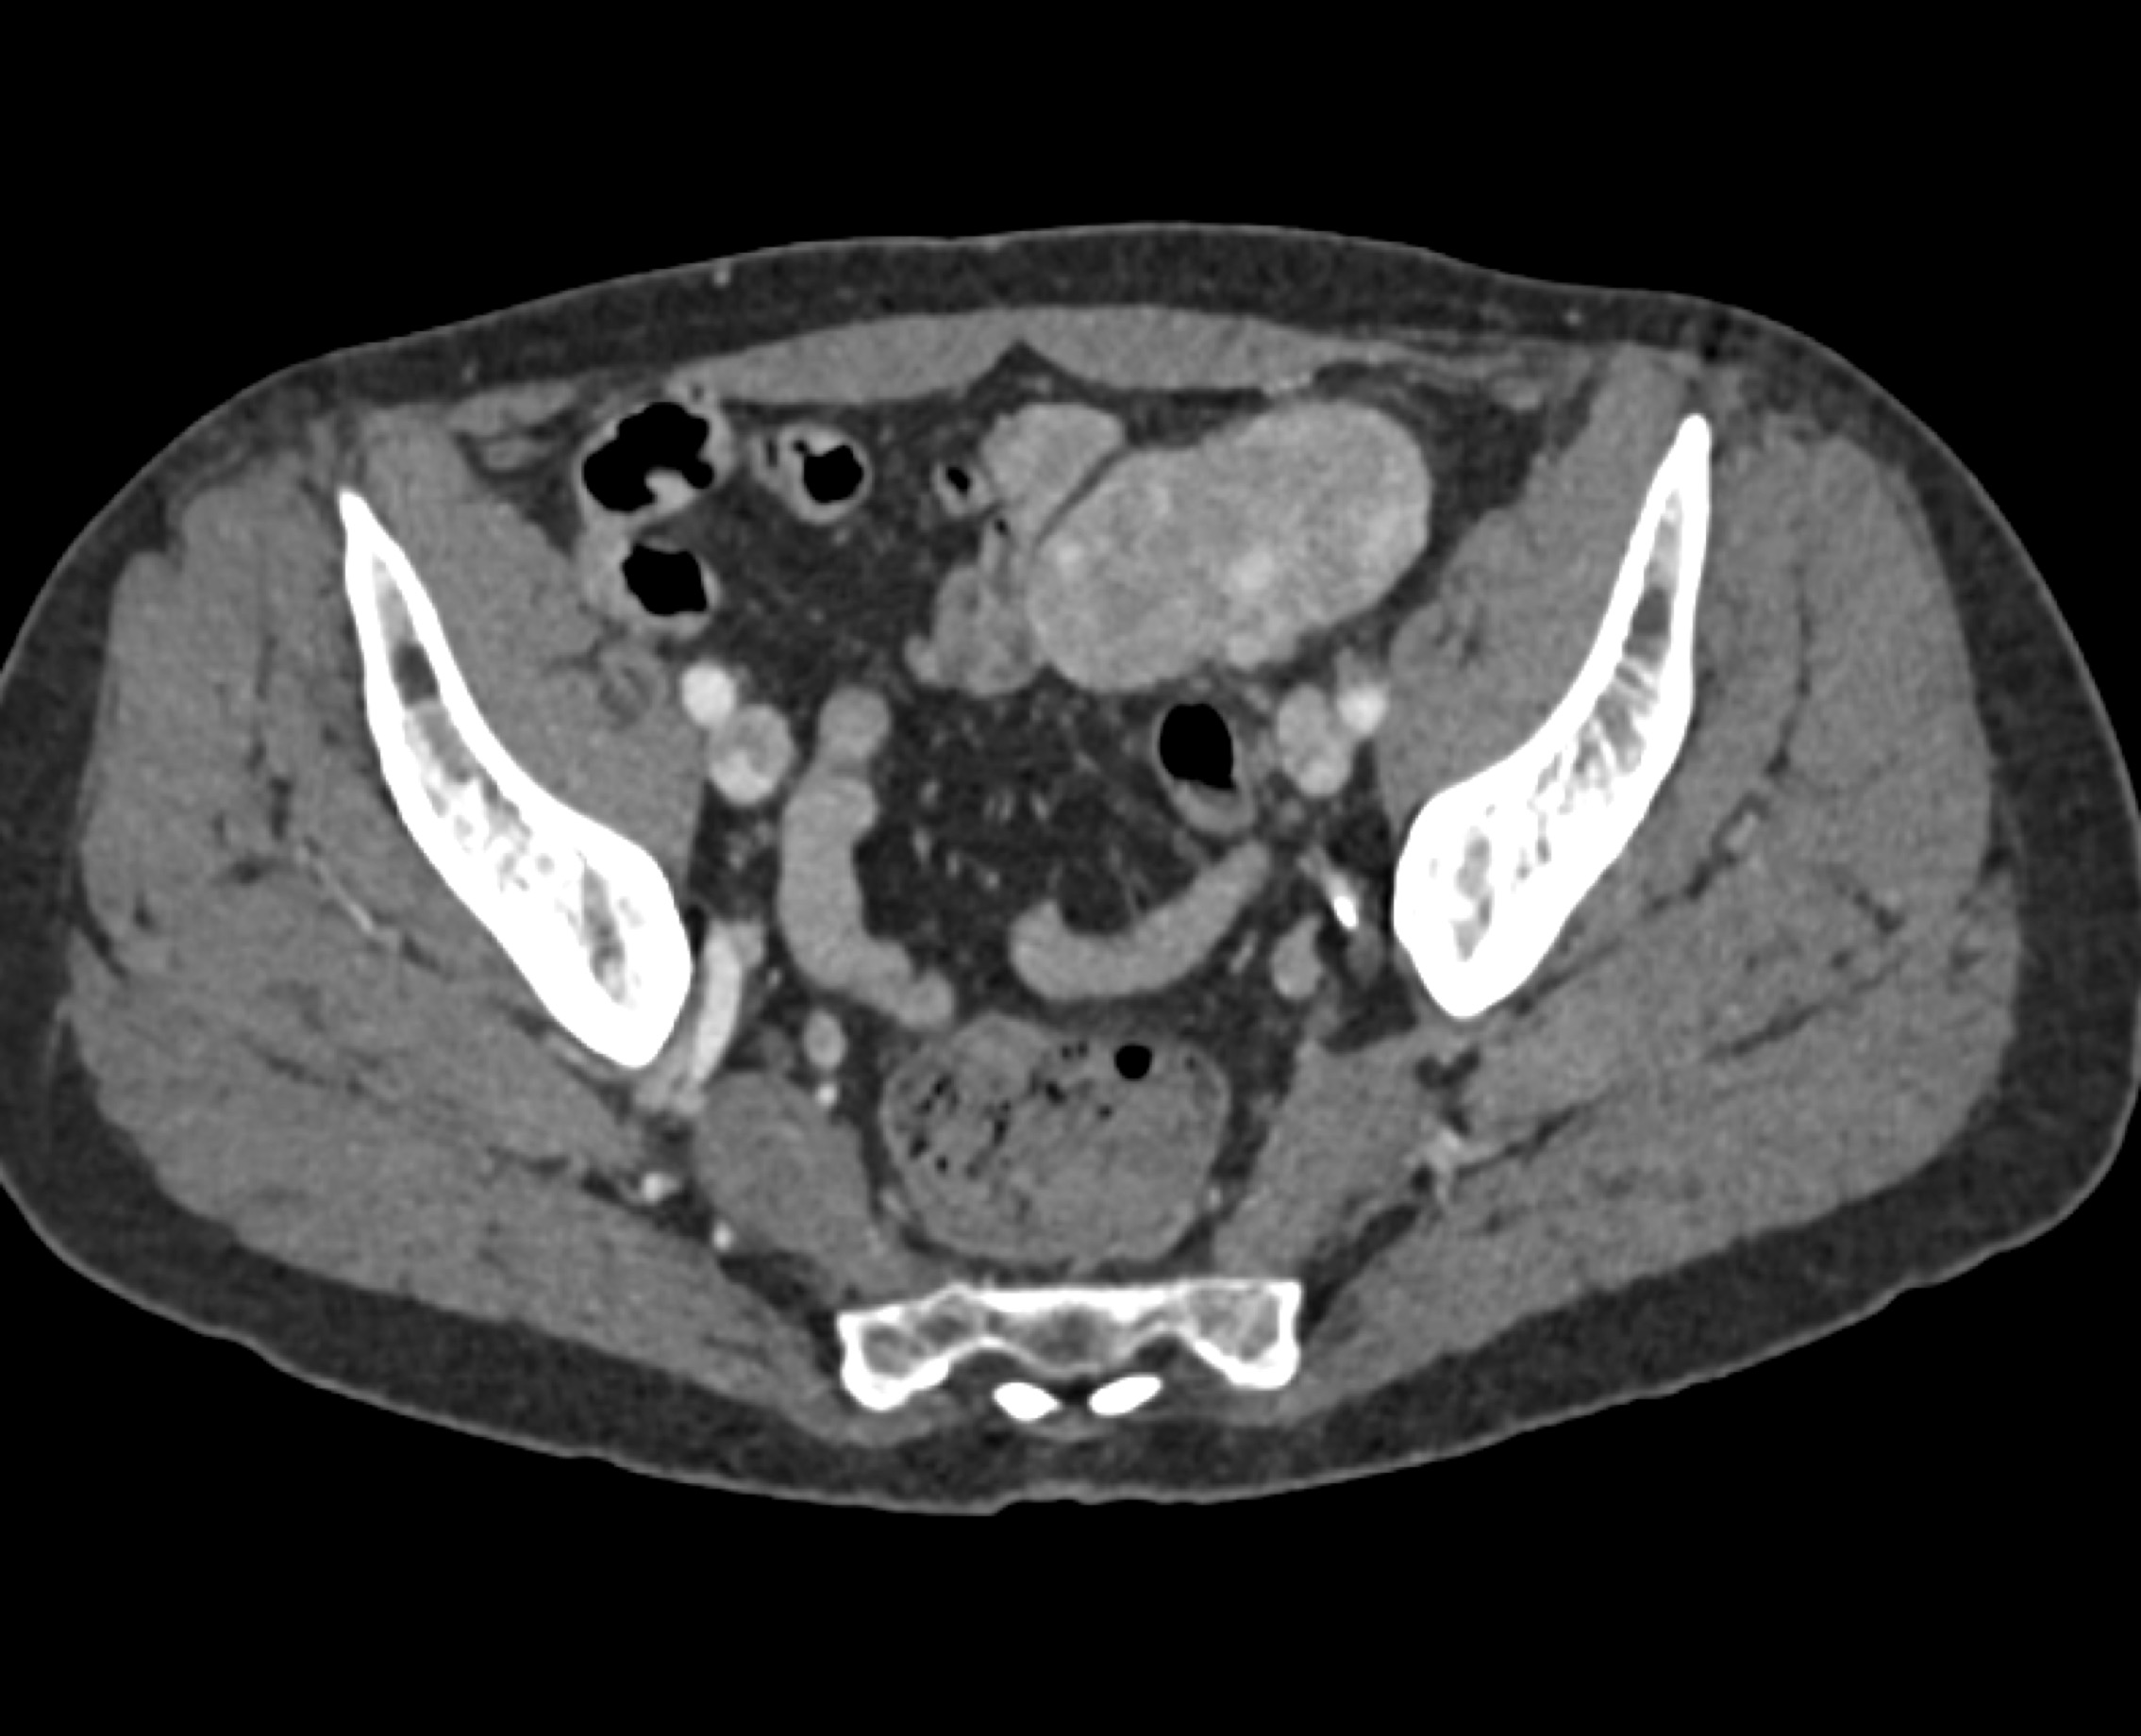

1) The most likely diagnosis in this case is?

lymphoma

Castleman disease

pheochromocytoma

paraganglioma